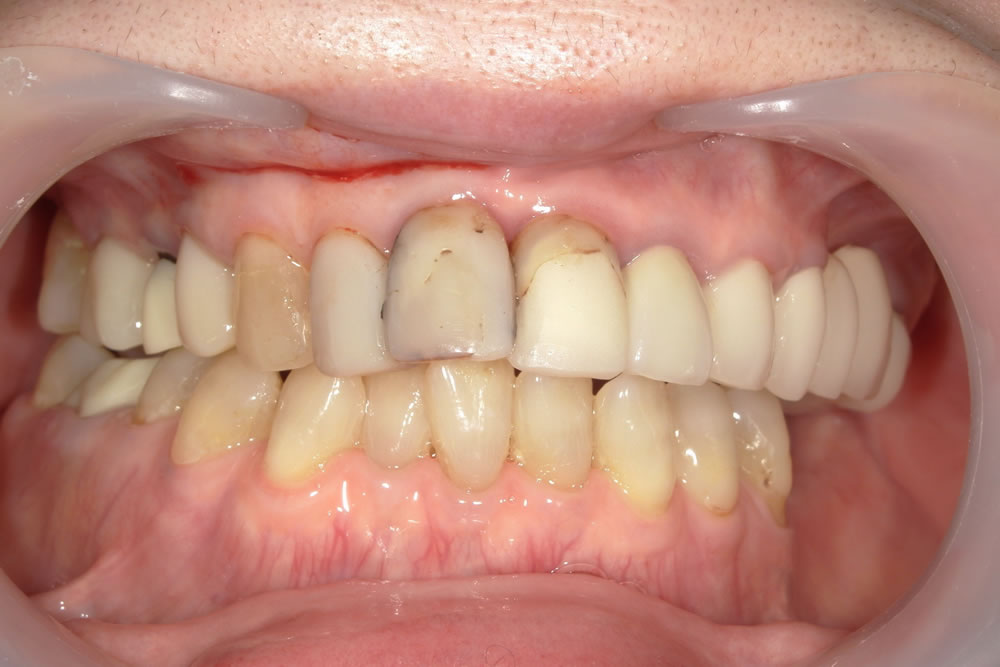

実績8000本以上のセラミック。自然で美しい口元へ

機能性と審美性を両立させた、オーダーメイドの白い歯

セラミック治療

銀歯を白くしたい、歯の色や形を整えたい、といったご希望に応えるのがセラミック治療です。見た目の美しさはもちろん、金属アレルギーの心配がなく、汚れが付着しにくいため虫歯の再発リスクを抑えられるという利点もあります。豊富な実績に基づき、一人ひとりの歯の色や形に調和した、自然な仕上がりを追求します。